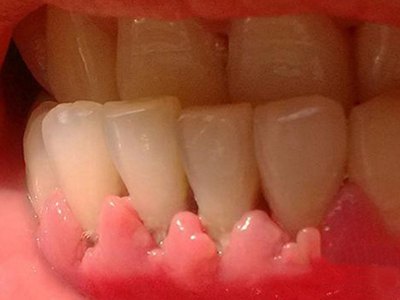

慢性龈炎的病损部位一般局限于游离龈和龈乳头,以前牙区为主,尤其以下前牙区最为显著,患者常因刷牙或咬硬物时牙龈出血而就诊。游离龈和龈乳头颜色变为鲜红或暗红色,病变较重时炎性充血可波及附着龈。龈缘变厚,龈乳头圆钝肥大,可增生呈球状,覆盖牙面。牙龈松软脆弱,缺乏弹性。

当牙龈以增生性反应为主时,龈缘和龈乳头呈坚韧的实质性肥大,质地较硬而有弹性。龈沟液量增多,还可能出现龈沟溢脓现象。

龈缘附近牙面上堆积的牙菌斑是引起慢性龈炎的始动因子,其他如牙石、食物嵌塞、不良修复体等均可促使牙菌斑积聚,引发或加重牙龈炎症。